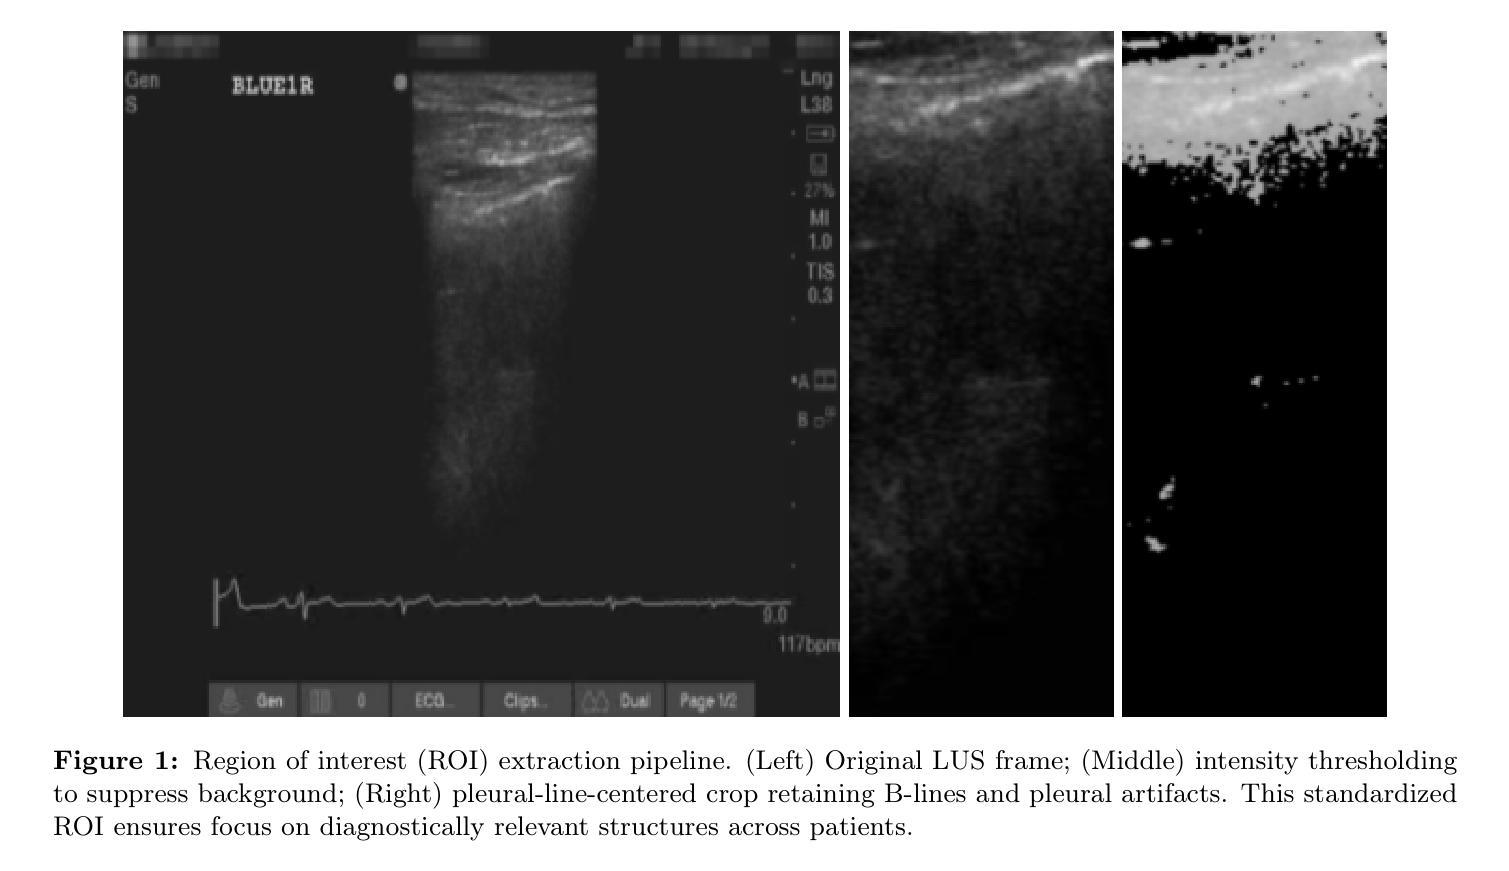

ZACH-ViT: A Zero-Token Vision Transformer with ShuffleStrides Data Augmentation for Robust Lung Ultrasound Classification

Authors:Athanasios Angelakis, Amne Mousa, Micah L. A. Heldeweg, Laurens A. Biesheuvel, Mark A. Haaksma, Jasper M. Smit, Pieter R. Tuinman, Paul W. G. Elbers

Differentiating cardiogenic pulmonary oedema (CPE) from non-cardiogenic and structurally normal lungs in lung ultrasound (LUS) videos remains challenging due to the high visual variability of non-cardiogenic inflammatory patterns (NCIP/ARDS-like), interstitial lung disease, and healthy lungs. This heterogeneity complicates automated classification as overlapping B-lines and pleural artefacts are common. We introduce ZACH-ViT (Zero-token Adaptive Compact Hierarchical Vision Transformer), a 0.25 M-parameter Vision Transformer variant that removes both positional embeddings and the [CLS] token, making it fully permutation-invariant and suitable for unordered medical image data. To enhance generalization, we propose ShuffleStrides Data Augmentation (SSDA), which permutes probe-view sequences and frame orders while preserving anatomical validity. ZACH-ViT was evaluated on 380 LUS videos from 95 critically ill patients against nine state-of-the-art baselines. Despite the heterogeneity of the non-cardiogenic group, ZACH-ViT achieved the highest validation and test ROC-AUC (0.80 and 0.79) with balanced sensitivity (0.60) and specificity (0.91), while all competing models collapsed to trivial classification. It trains 1.35x faster than Minimal ViT (0.62M parameters) with 2.5x fewer parameters, supporting real-time clinical deployment. These results show that aligning architectural design with data structure can outperform scale in small-data medical imaging.

Summary

针对肺超声视频中心源性肺水肿(CPE)与非心源性及结构正常肺部的区分,仍存在挑战。提出一种名为ZACH-ViT的新型视觉转换器,可在无序医学图像数据上实现全自动分类。通过ShuffleStrides数据增强方法提高通用性,并在380个肺超声视频上进行评估,结果显示ZACH-ViT在异质非心源性疾病组中具有最佳验证和测试ROC-AUC值,且训练速度快、参数少,适合实时临床部署。